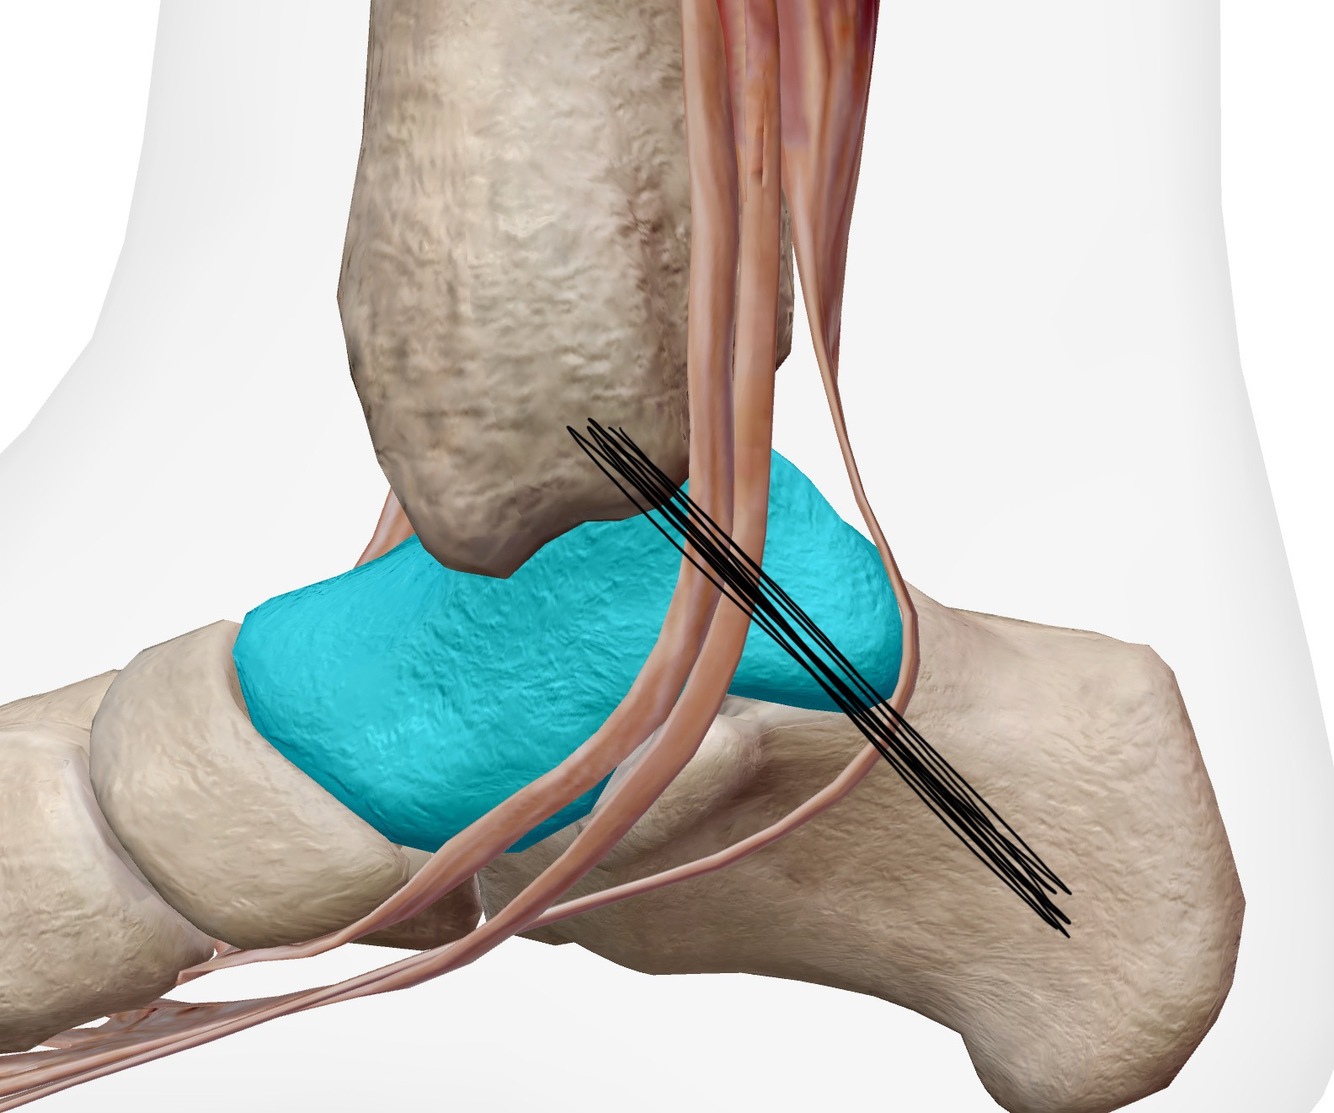

Place ta sonde sur l’image où le nerf tibial va se diviser en ses 2 branches, donc ou tu devrais le mesurer en court axe dans ton évaluation du syndrome du tunnel tarsien